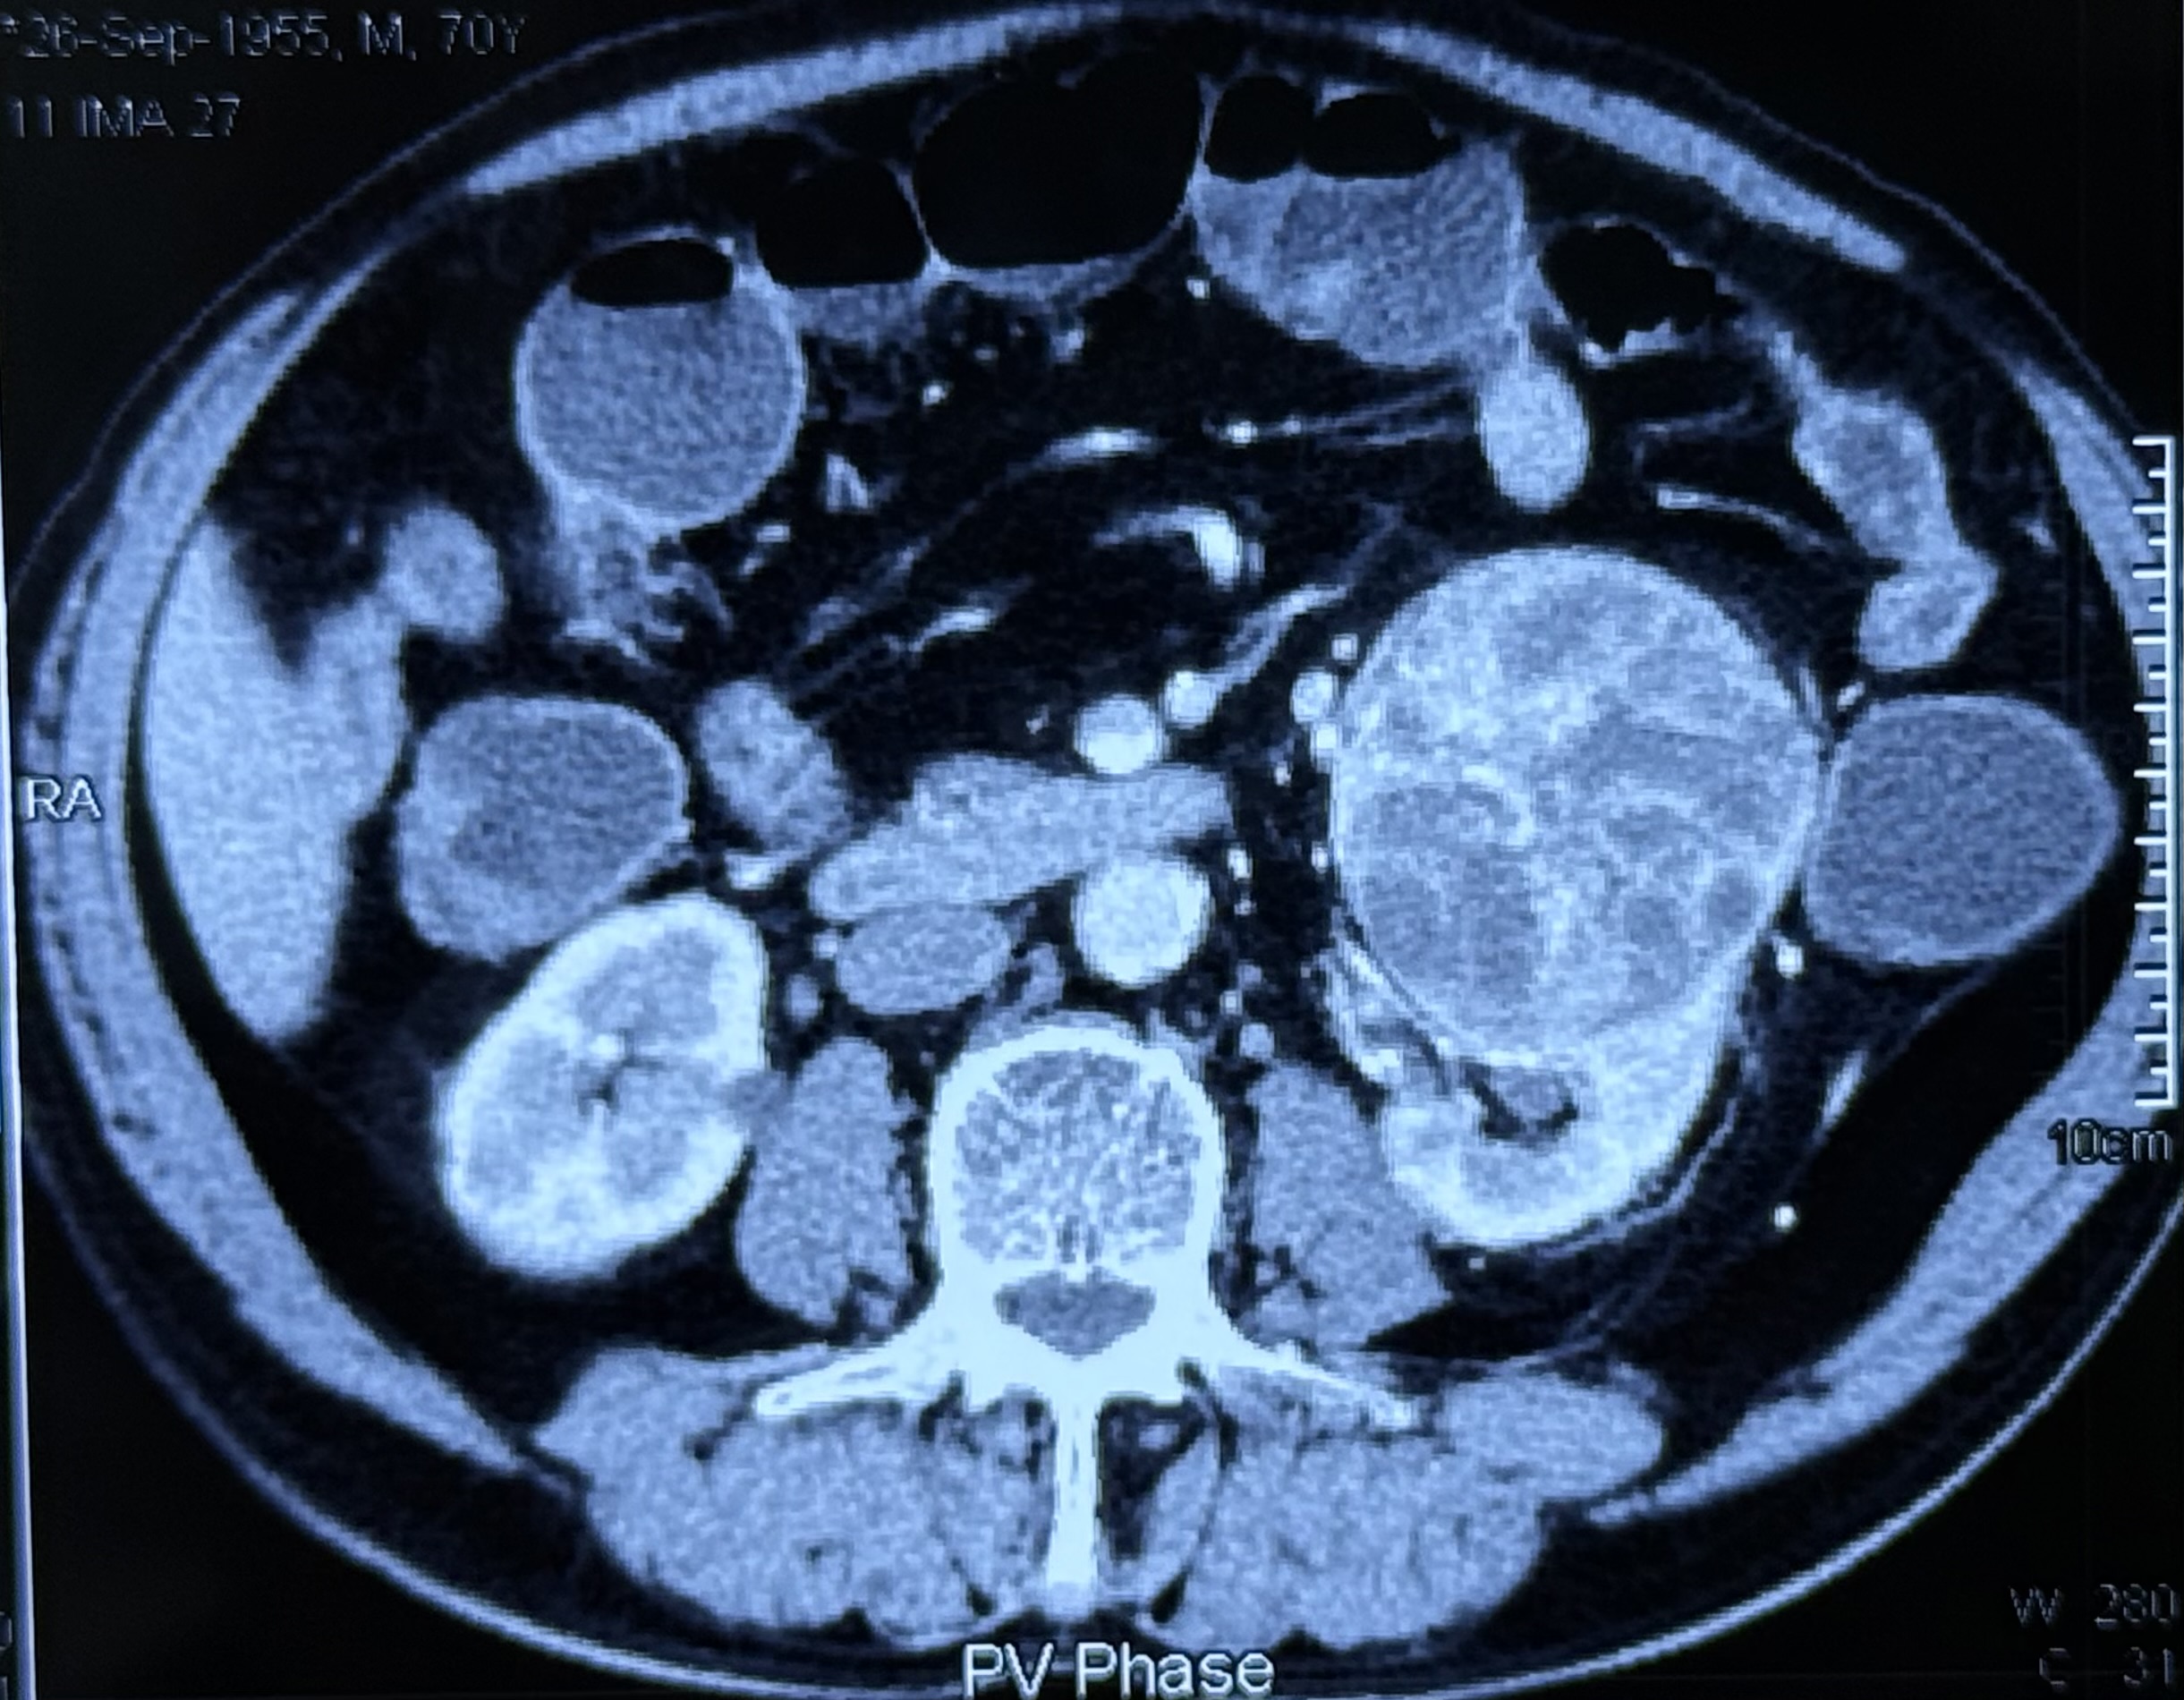

mRCC treated with IO-TKI

Excellent prognosis even in case of metastatic renal clear cell carcinoma Both the study with Pembro + Axi (KEYNOTE-426) & Nivo + Cabo (CheckMate-9ER) showed Comparable OS/ORR; Nivo+Cabo with slightly stronger PFS, Pembro+Axi with longest OS follow-up.